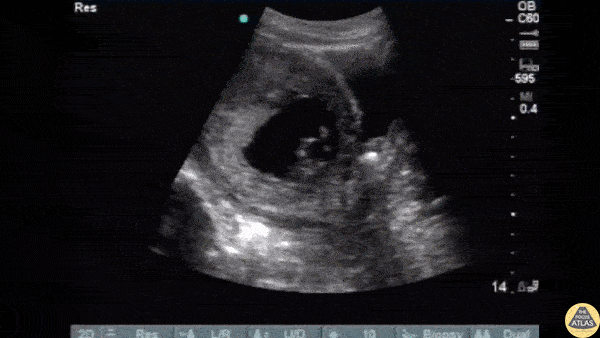

Renal/GU - Ureteral Stone during Pregnancy

A pregnant female of 8 week gestation presented to the ED with sudden severe right adnexal pain with stable vitals. Ultrasound revealed a viable IUP and a stone within the right distal ureter. Image courtesy of Robert Jones DO, FACEP @RJonesSonoEM Director, Emergency Ultrasound; MetroHealth Medical Center; Professor, Case Western Reserve Medical School, Cleveland, OH View his original post here